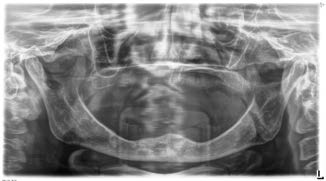

Trước khi bắt đầu quy trình cấy ghép Implant ngắn 6.5mm BTI, tất cả bệnh nhân tiêu xương dọc đều trải qua quy trình chẩn đoán toàn diện, bao gồm chụp cắt lớp vi tính chóp nón (CBCT), mẫu hàm nghiên cứu và sáp chẩn đoán (diagnostic wax-ups). Phân tích 3D của phần xương còn lại giúp xác định vị trí, góc độ và đường kính Implant một cách chính xác.

Có 18 bệnh nhân đã nhận 36 Implant ngắn 6.5mm BTI phục hình liên kết dưới dạng chịu lực tức thì. Thời gian theo dõi trung bình là 8.02 ± 1.47 năm (dao động từ 6 đến 10 năm).

- Đa số các Implant ngắn 6.5mm BTI (69.4%) được đặt ở vùng răng hàm dưới chịu ảnh hưởng của tình trạng tiêu xương dọc.